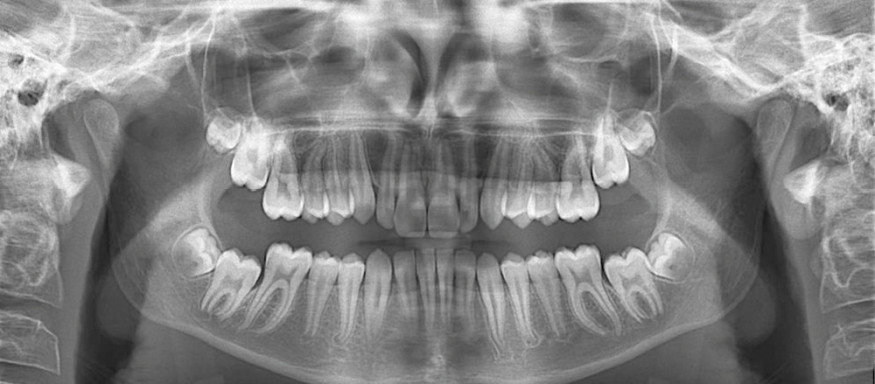

Maxime, âgé de 13 ans et 3 mois, se présente à la consultation, adressé par son chirurgien-dentiste.

Son profil convexe s’inscrit dans un contexte de classe II squelettique par rétrognathie mandibulaire normodivergente sur un schéma de Classe II/2 avec supraclusion et encombrement modéré (fig. 1 à 7).

La formule dentaire est complète, avec un léger retard d’évolution des deuxièmes molaires (fig. 8).

La classe II squelettique est objectivée par l’angle ANB = 7,6° confirmée par l’AoBo = 7,6 mm l’étiologie étant d’origine mandibulaire SNB = 69,9° (fig. 9 et 10).